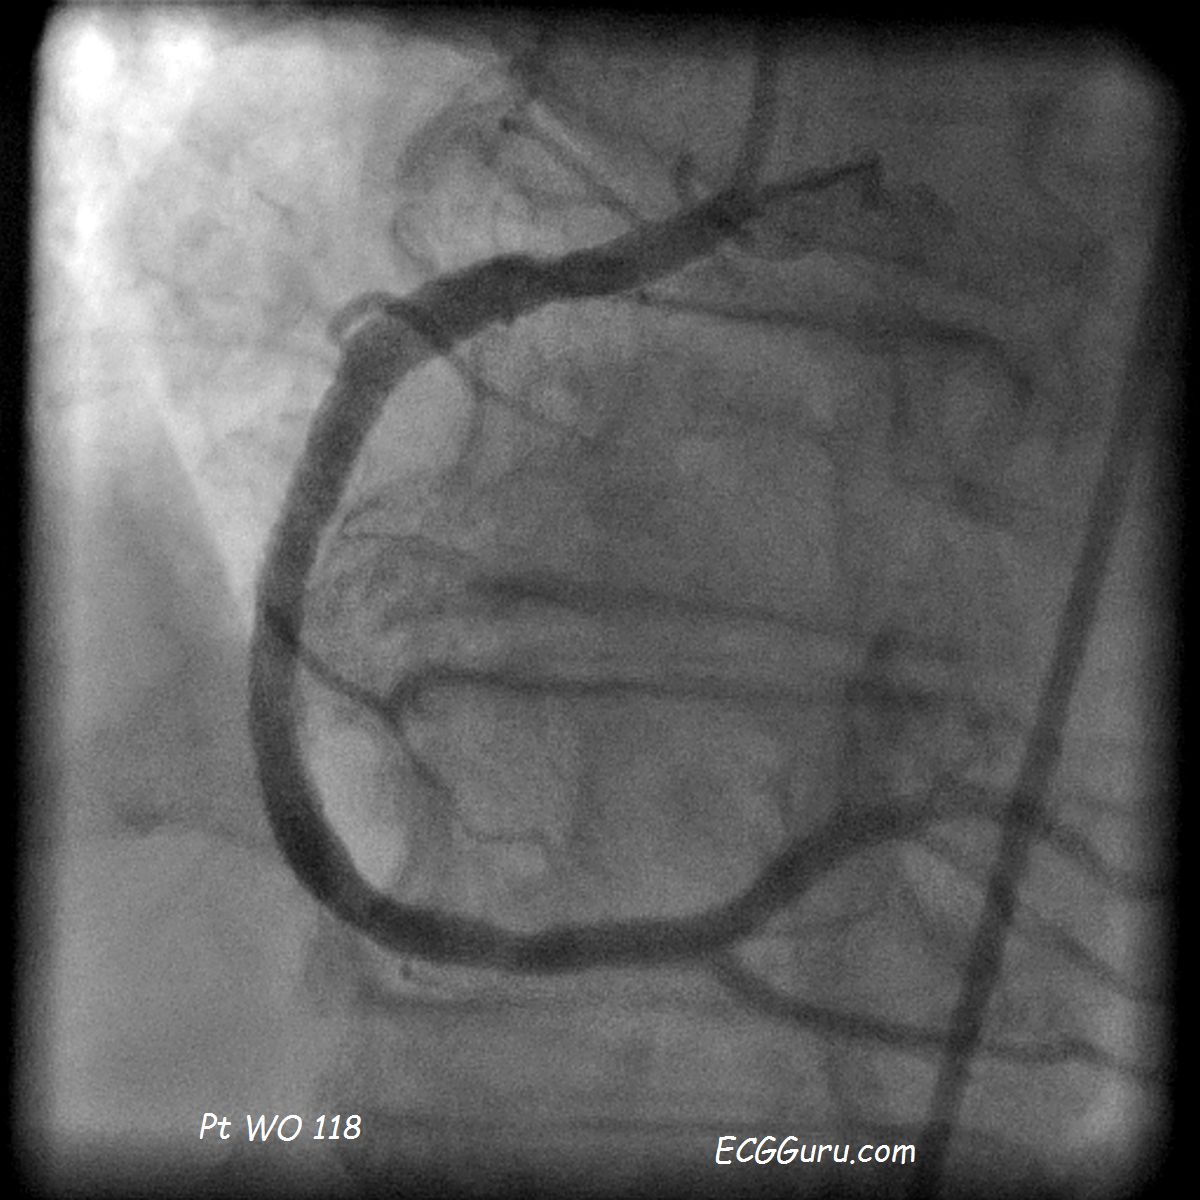

Right Coronary Artery with severe disease